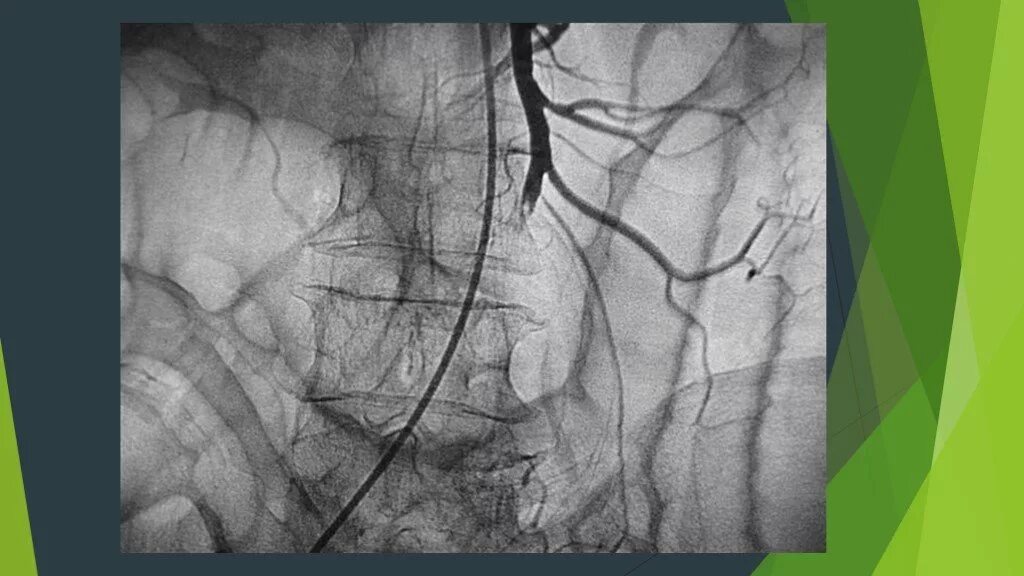

Тромбоз брыжеечной артерии